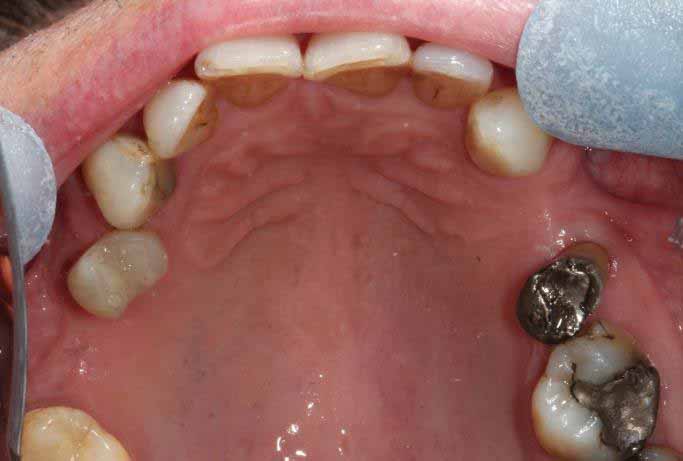

Full Mouth Rehabilitation

Full mouth Treatment – missing upper front teeth and mispositioned implants in the Lower left side meant planning was key here to get the desired result. Implants were placed to replace the missing teeth, veneers/crowns on the remaining upper teeth allowing an improvement in overall shape and colour, and the implant crowns on the lower left were change to bring into the line of the bite.